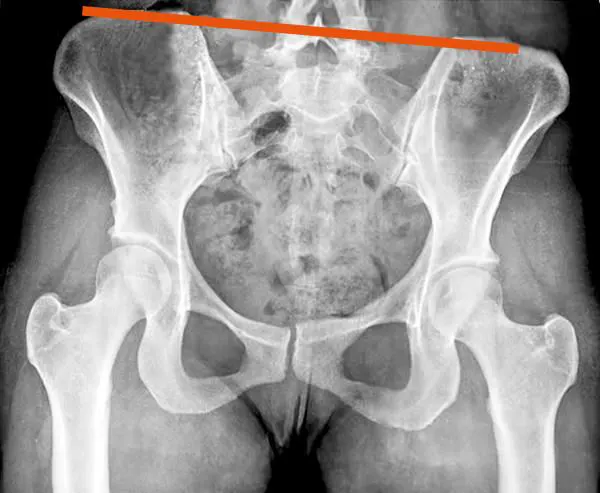

تشخيص اعوجاج الحوض: كيف يحدد الطبيب المشكلة بدقة؟

يعتمد تشخيص اعوجاج الحوض على تقييم دقيق للقوام والحركة.

يبدأ الطبيب عادة بالفحص السريري لملاحظة وضع الحوض والعمود الفقري أثناء الوقوف والمشي.

قد يشمل التقييم أيضًا:

- فحص توازن العضلات ومرونتها

- قياس محاذاة الحوض

- تقييم طول الساقين

وفي بعض الحالات قد تُستخدم الأشعة السينية أو الفحوصات التصويرية الاخرى للتأكد من وجود أي أسباب هيكلية تؤدي إلى ميلان الحوض.